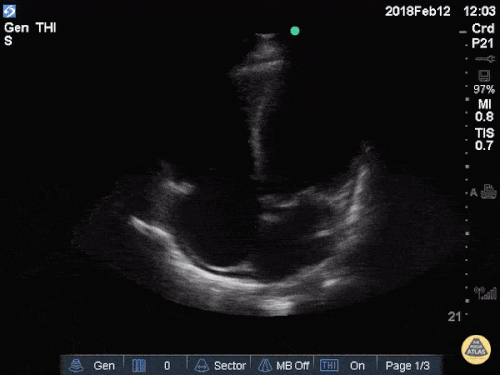

Perikarderguss/Tamponade

Der Perikarderguss, bzw. die Maximalvariante – die Tamponade – ist eine sonographisch leicht zu diagnostizierende Erkrankung, sowohl mit einem Konvex- (=Abdomen-) als auch einem Echoschallkopf. Am einfachsten gelingt der Nachweis von subxiphoidal. Der Schallkopf wird unterhalb des Xiphoids aufgesetzt und so unter die Rippen gekippt, dass das Herz zum Vorschein kommt. Hier kann man einen (relevanten) Erguss rasch erkennen. Zeichen für eine hämodynamische Relevanz sind z.B. die Kompression des rechten Vorhofs und des Ventrikels.

Quelle: http://www.thepocusatlas.com/pericardium CC BY-NC 4.0